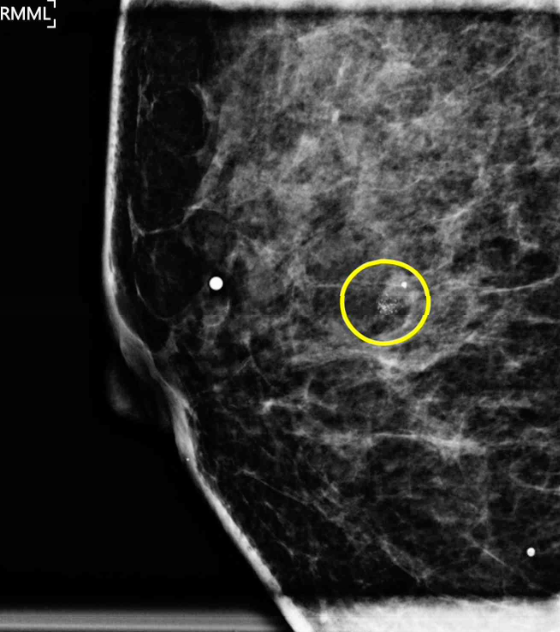

40세 여자가 유방암 검진에서 오른쪽 유방에 미세한 석회음영이 보인다고 병원에 왔다. 3년 전에 받은 유방 검진에서는 이상이 없었다고 한다. 혈압 125/85 mmHg, 맥박 60회/분, 호흡 12회/분, 체온 36.4°C이다. 오른쪽 유방에서 만져지는 덩이는 없다. 유방초음파에서 오른쪽 유방의 미세한 석회음영과 일치하는 1cm 크기의 병변을 확인하였다. 유방확대촬영 사진이다. 초음파 유도 중심부바늘생검 검체촬영에서 미세한 석회가 확인되었다. 유방조직검사 결과는 다음과 같다. 조치는?

MAM: grouped, fine pleomorphic calcification in Rt. breast

• MAM상 grouped, fine pleomorphic calcification이 확인되므로 악성 종양에 대한 감별이 필요하며, 이는 조직검사를 통해 이루어진다.

• 해당 증례에서는 초음파로 MAM의 미세석회음영과 일치하는 병변을 확인할 수 있었으므로 US-guided core needle biopsy로 조직검사를 시행하였다. 검체에서 미세한 석회가 확인되었다는 언급으로 보아 targeted lesion을 적절하게 획득한 것으로 판단할 수 있다.

• 해당 MAM에서 확인되는 석회화 및 병변의 양상을 고려할 때, 영상학적으로는 악성이 의심되어 BI-RADS 4a~4b 범주에 해당한다고 볼 수 있다. 현재 조직검사 결과는 양성 종양인 섬유샘종으로 나타났으므로, imaging-histologic correlation을 고려할 때 양성 결과와 영상 소견이 불일치(discordant benign)하므로 재검을 고려하는 것은 타당하다. 최초 조직검사는 중심침생검으로 시행되었으므로, 재검 시에는 충분한 조직 채취가 가능한 다음 단계의 생검 방법인 수술적 생검(예: 절제 생검 등)을 선택해야 한다. 그러나 해당 선택지에는 이를 반영한 옵션이 없는 것으로 보인다. Imaging-histologic correlation을 판단하기 위해서는 단일한 악성 의심 소견만을 기준으로 판단하는 것이 아니라, BI-RADS 분류를 기반으로 한 정확한 영상학적 평가가 필요하다. 다만 본 문제에서는 BI-RADS 분류가 제시되지 않은 바, 학부 수준에서 MAM/US 사진만으로 BI-RADS 카테고리를 정확히 판단하여 진단 알고리즘을 고려하는 것은 국시의 출제 의도와 맞지 않는 것으로 보인다. 따라서 본 문제는 재검을 요하는 경우 충분한 조직 채취가 가능한, 다음 단계의 생검 방법(1st core needle Bx → 2nd surgical Bx)을 택해야 한다 정도의 지식으로 해결하는 것이 적절할 것으로 판단된다.